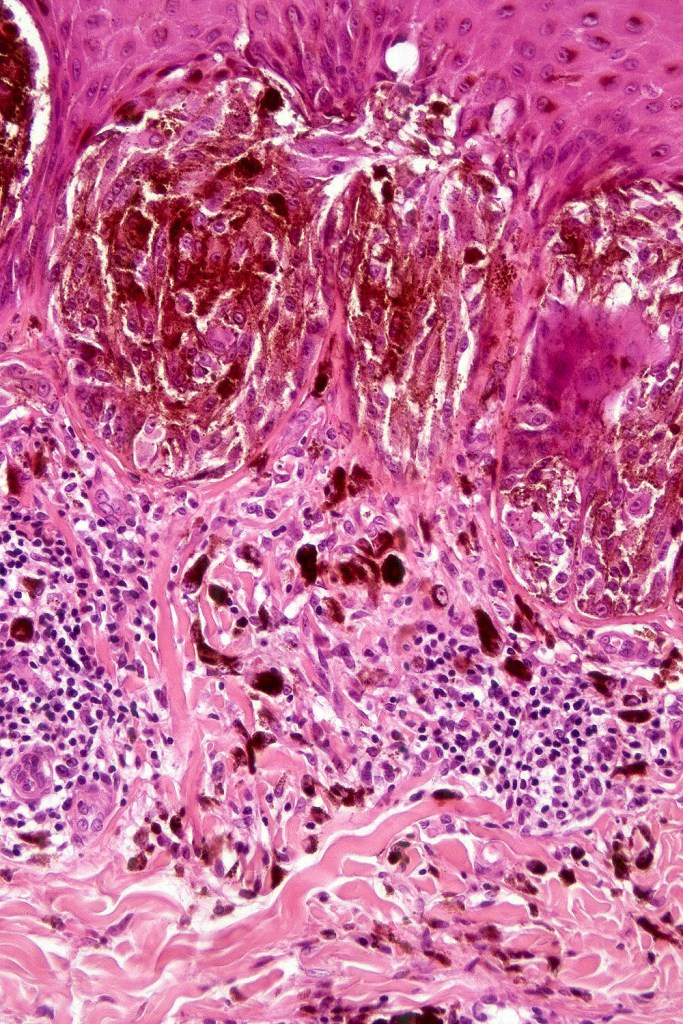

•Vertically orientated oval junctional nests

. Heavy pigmentation although hypopigmented/amelanotic varinats can be encountered

•Junctional or compound

•Acanthosis & hyperkeratosis

•Central focal Pagetoid spread & elimination of nests sometimes seen

. Lymphocytic infiltrate often seen at base